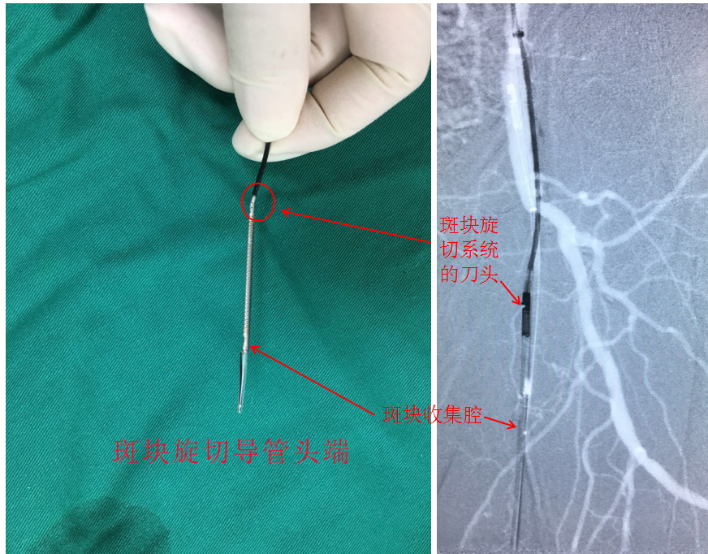

斑块定向旋切(Directional Atherectomy, DA)是指以控制和定向的方式从动脉壁中主动清除斑块,将切除的斑块直接收集到导管头端的锥形容器中,旋切完成后将导管和斑块一起取出。我们为王大爷实施微创治疗所采用的是美国的Turbohawk斑块旋切导管,将带有旋切刀片的导管送入病变部位的动脉腔内,这个旋切导管有四组锥形刀片,通过高速的旋转从而可以在一次通过病变中切除更多的斑块,甚至对于钙化特别严重的斑块,旋切也有很好的效果(图6)。

图6 斑块切除导管实物图